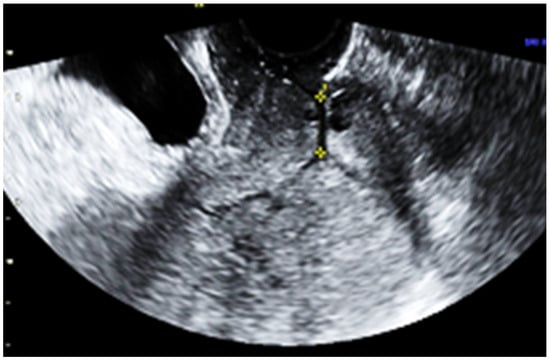

Subsequent ultrasound examination revealed a uterus with a homogeneous structure measuring 67/52/61 mm (Figure 1). However, in the lower portion of the uterine cavity and the upper part of the cervical canal, there was a non-homogeneous hyperechogenic mass measuring 72/30/75 mm (Figure 2). The mass exhibited numerous vessels (Figure 3), while the lower portion of the cervix appeared normal with a length of approximately 13 mm (Figure 4).

Figure 4.

The lower part of the uterine cervix with normal characteristics.